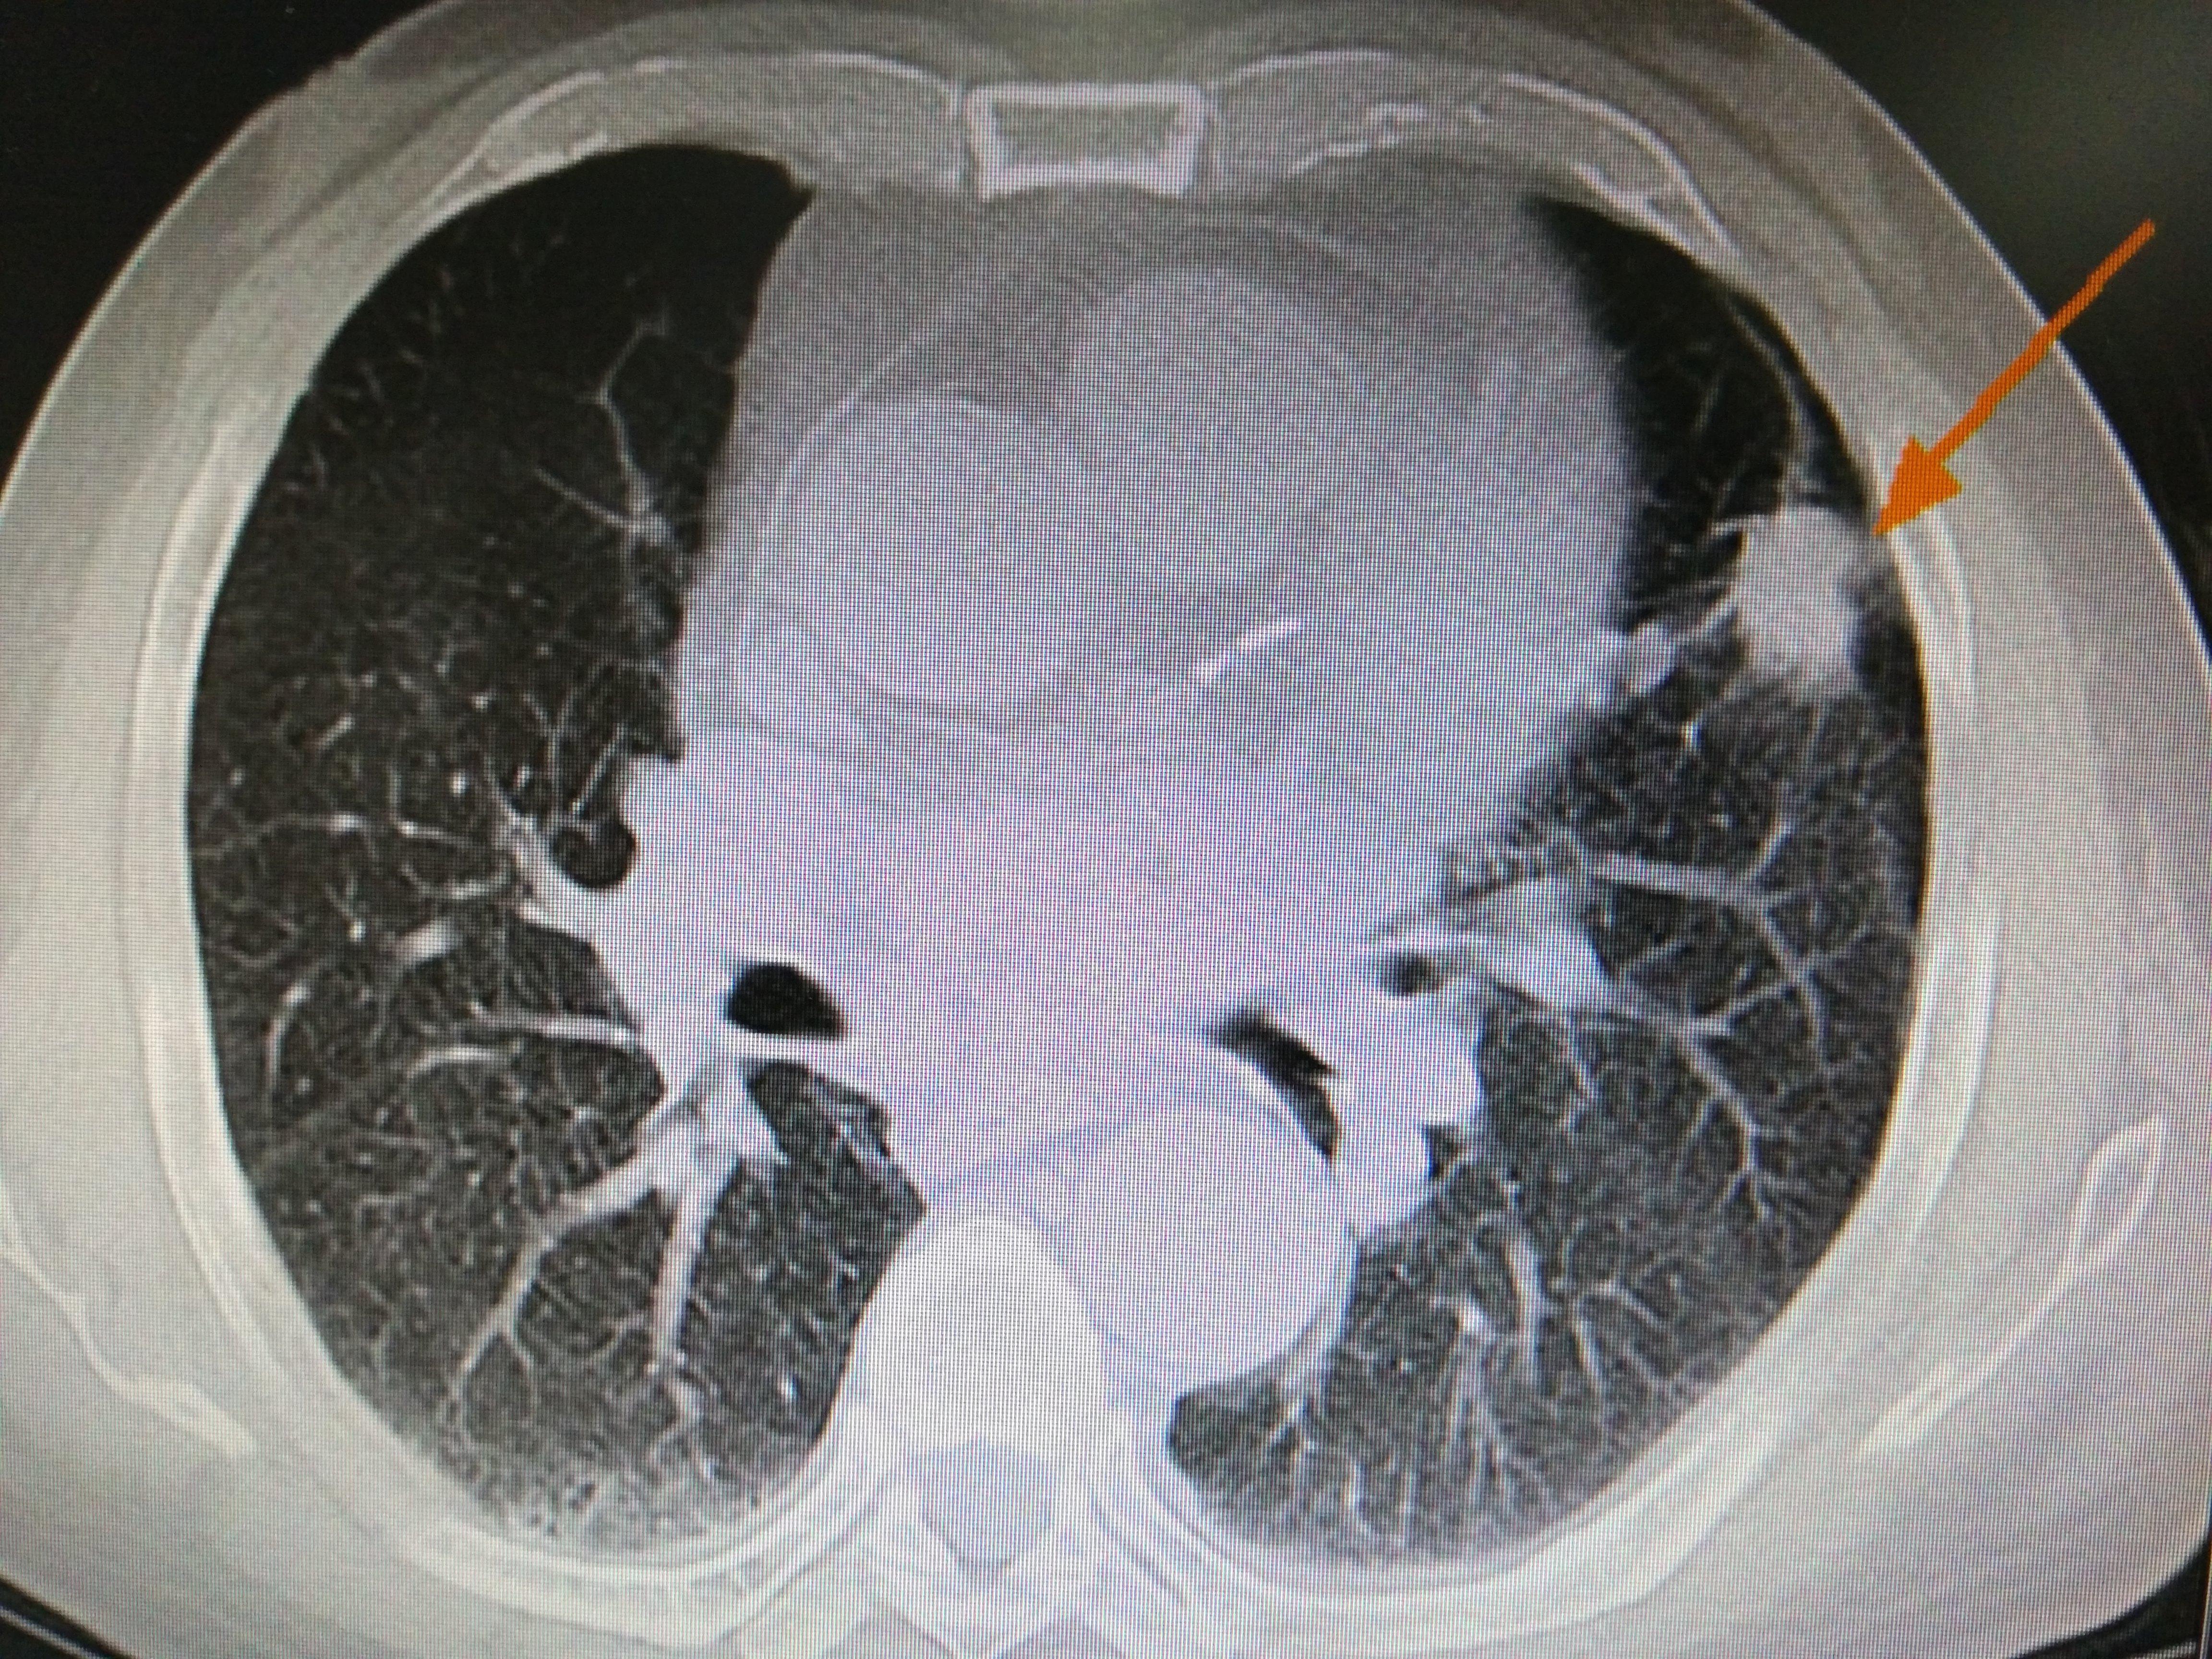

怎么办,当然是首选射频消融,两根消融针,形成立体靶向消融场。4cm结节,一次治疗搞定!20min,几乎无痛,无创伤!治疗后,胸痛是立马缓解,不需要吃止痛片。肿块很快就缩小。再配合线粒体靶向治疗。病灶一直持续缩小,处于稳定状态。

射频治疗2月后。